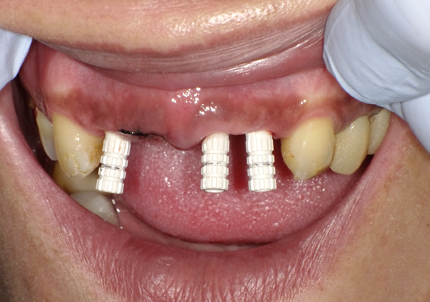

患者:Y.S 様

初診日 :2018年10月

主訴 :上顎前歯部審美障害、臼歯部補綴治療

1.初診時口腔内写真(2018年10月)